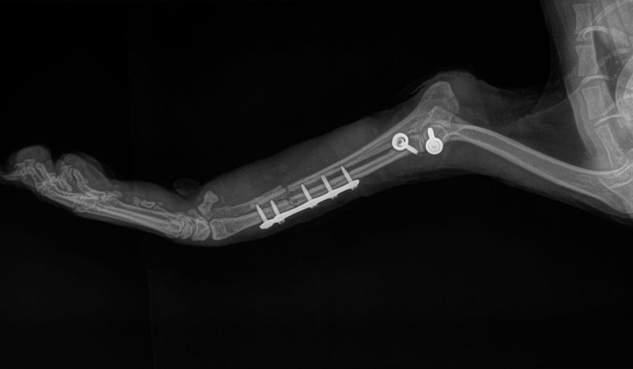

Ortopedia:

Área de la medicina veterinaria encargada del diagnóstico y tratamiento de enfermedades que afectan el sistema músculo esquelético (huesos, articulaciones, ligamentos, tendones) Así como el tratamiento de las mismas. Incluye cirugías de alta especialidad.